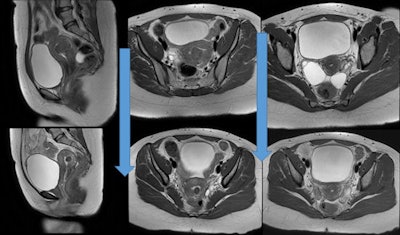

In this study, most women opted for UFE as a fertility treatment after failure of myomectomy or in vitro fertilization, or because hysterectomy was the only suggested option. Of the 210 patients who received UFE treatment, 35 women younger than the age of 40 wanted to conceive and had been unable.

Premature menopause, hysterectomy, and radiation exposures have been identified as barriers to fertility when treating women with UFE, and they might occur with other known UFE complications in a very small number of patients, less than 4%. However, uterine fibroids themselves rarely cause infertility, but they may be a causative factor of pregnancy loss. The study participants were advised to wait six months or more after UFE before attempting to conceive, of which the reported time range before attempting to conceive was seven to 33 months (average 20 months).

In a retrospective chart review of patients younger than the age of 40 (35 patients) who wished to spare their fertility and underwent UFE from 2011 to 2016, 18 patients reported 23 pregnancies, of which five were miscarriages. Two more pregnancies were complicated by premature labor. Of the 23 pregnancies, 16 were normal full-term pregnancies, 15 women had become pregnant once, and four had become pregnant twice.

The remaining patients did not conceive. In the study, there was no reported intrauterine growth retardation in the prenatal period, fetal distress during labor, or problems related to uterine integrity. Two patients reported minor problems during pregnancy that were borderline oligohydramnios and low-lying placenta.

In the cohort of women who did conceive, overall, 16 out of 18 births proceeded normally without any complications (86%). Eight women delivered by cesarean section, and 10 women had normal vaginal delivery.